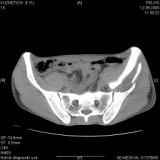

Уважаемые коллеги! Хотелось бы услышать совет по тактике лечения представлленого больного.

Поступил после лечения в одном изотделений области. Травма 2,5 месяца назад.

После выведения

из шока был произведен остеосинтез перелома бедра, предплечья, до перевода к нам проводилось

вытяжение по оси шейки бедра за стержень, введенный в большой вертел. На сегодня деформация

ригидна, клинически мобильности не определяется.